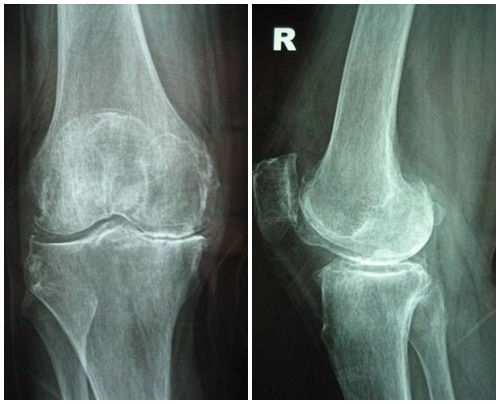

Hình ảnh của khớp gối trên phim X-quang: Khe khớp hẹp nhẹ, có gai xương nhỏ.

Thoái hóa khớp gối giai đoạn 2 vẫn là giai đoạn nhẹ

Giai đoạn 2 vẫn được xem là giai đoạn tiến triển nhẹ, xem trên phim X-quang có thể thấy kích thước bề mặt sụn khớp vẫn chưa có sự thay đổi nhiều. Bao hoạt dịch khớp vẫn hoạt động bình thường, cung cấp đủ dịch khớp để nuôi dưỡng sụn và bôi trơn ổ khớp, giúp các đầu xương hoạt động được trơn tru. Mặc dù vậy, bệnh nhân vẫn có thể xuất hiện một số triệu chứng như đau mỏi ở khớp gối sau khi vận động nhiều hoặc khi làm việc quá sức, làm việc sai tư thế; cứng khớp khi trời lạnh hoặc do ít vận động khớp.